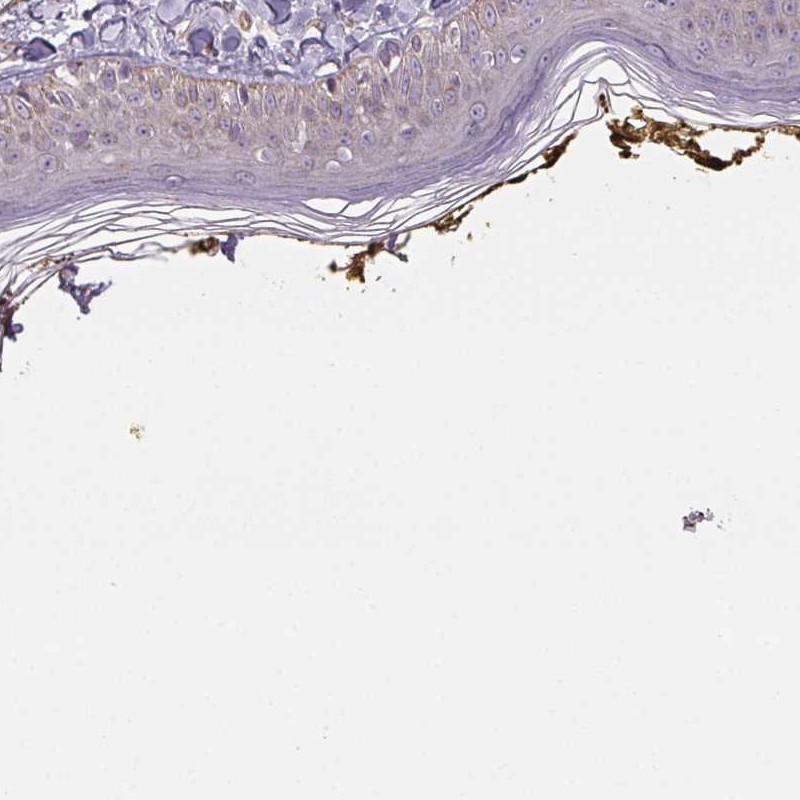

Immunohistochemistry analysis in human skin and liver tissues using Anti-PLA2G4F antibody. Corresponding PLA2G4F RNA-seq data are presented for the same tissues.